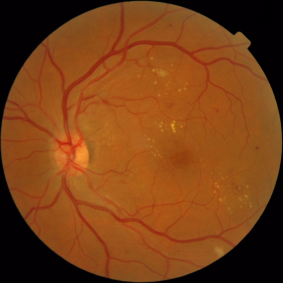

Retinal pathologies are responsible for millions of blindness cases worldwide. The leading causes of blindness are glaucoma (4.5 million cases), age-related macular degeneration (3.5 million cases) and diabetic retinopathy (2 million cases).111www.who.int/blindness/causes/priority Early diagnosis is the key to slowing down the progression of these diseases and therefore preventing the occurrence of blindness. In the case of diabetic retinopathy (DR) screening, diabetic patients have their retinas examined regularly: a trained reader searches for the early signs of the pathology in fundus photographs (see Fig. 1) and decides whether the patient should be referred to an ophthalmologist for treatment. In order to reduce the workload of human interpretation, and therefore streamline retinal pathology screening, various image analysis algorithms have been developed over the last few decades. The first solutions were trained to detect lesions (at the pixel level) using manual segmentations (at the pixel level) for supervision (Winder et al., 2009; Abràmoff et al., 2010): this is what we call computer-aided detection (CADe) algorithms. Based on the detected lesions, other algorithms were trained to detect pathologies (at the image level) (Abràmoff et al., 2010): this is what we call computer-aided diagnosis (CADx) algorithms. In recent years, new algorithms were designed to detect pathologies directly, using diagnoses (at the image level) only for supervision: these algorithms are based on multiple-instance learning (Quellec et al., 2017; Manivannan et al., 2017) or deep learning (LeCun et al., 2015). Because manual segmentations are not needed, such algorithms can be trained with much larger datasets, such as anonymized archives of examination records. The next challenge is to detect lesions using diagnoses only for supervision. Besides access to large training datasets, such an approach would allow discovery of new biomarkers in images, since algorithms are not limited by the subjectivity of manual segmentations. A few multiple-instance learning algorithms, supervised at the image level, can already detect lesions (Melendez et al., 2015; Quellec et al., 2016b). However, to our knowledge, no deep learning algorithm was designed to solve this task. The primary objective of this study is to find a way to detect lesions, or other biomarkers of DR, using deep learning algorithms supervised at the image level. A secondary objective is to use these local detections to improve DR detection at the image level.

In 2015, a machine learning competition was organized with the goal to design an automated system for grading the severity of diabetic retinopathy (DR) in images.222https://www.kaggle.com/c/diabetic-retinopathy-detection Images were trained and evaluated at the image level in a publicly-available dataset of almost 90,000 images provided by EyePACS (Cuadros and Bresnick, 2009), a free platform for DR screening. The performance criterion was the inter-rater agreement between the automated predictions and the predictions of human readers. As usual in recent pattern recognition competitions (Russakovsky et al., 2015), the top-ranking solutions all relied on deep learning. More precisely, they relied on ensembles of ConvNets. ConvNets are artificial neural networks where each neuron only processes one portion of the input image (LeCun et al., 2015). The main building-block of ConvNets are convolutional layers. In those layers, input images are convolved with multiple filters inside a sliding window (tens or hundreds of 3 3 to 5 5 multichannel filters, typically). After nonlinear post-processing, one activation map is obtained per filter. Those activation maps can be further processed by another convolutional layer, or can be nonlinearly down-sampled by a pooling layer. After several convolutional and pooling layers (10 to 30 layers, typically), ConvNets usually end with dense layers, which produce image-level predictions. Overall, ConvNets usually have a few million free parameters. The inter-rater agreement achieved by solutions of the challenge was clearly at the level of the inter-rater agreement among human readers (Barriga et al., 2014). However, many clinicians would not trust a black box, like a ConvNet (not to mention an ensemble of ConvNets), if their patient’s health and their liability are at stake. Therefore, we are looking for a solution that jointly detects referable DR at the image level and detects biomarkers of this disease at the pixel level. Because of their good performance, solutions of the Kaggle DR challenge were reused and modified to also provide pixel-level detections. The proposed modifications rely on ConvNet visualization techniques. The resulting solution is part of the Messidor® system for eye pathology screening,333http://www.retinoptic.fr/ which integrates a mobile non-mydriatic retinograph and algorithms for automated or computer-aided diagnosis.